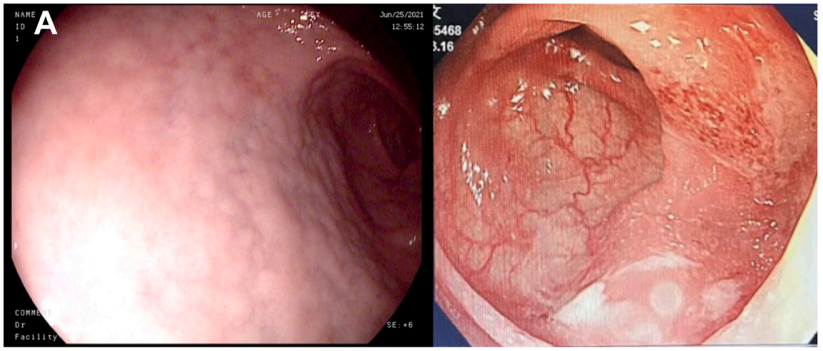

病史摘要:患者为 38 岁男性,因“发现乙肝 1 月余,腹痛 1 天”入院。1 月前诊断为“失代偿期肝硬化(脾大、腹水、门脉高压、食管静脉曲张)乙肝”,经抗 HBV、保肝治疗后症状缓解。入院前 1 天突发剑突下疼痛,进食后稍缓解,入院当日腹痛加重,伴恶心、呕吐。有吸烟及不规律饮酒史,现已戒酒,母亲因“肝硬化”去世,无慢性基础疾病、手术史、过敏史及有毒有害物质接触史。